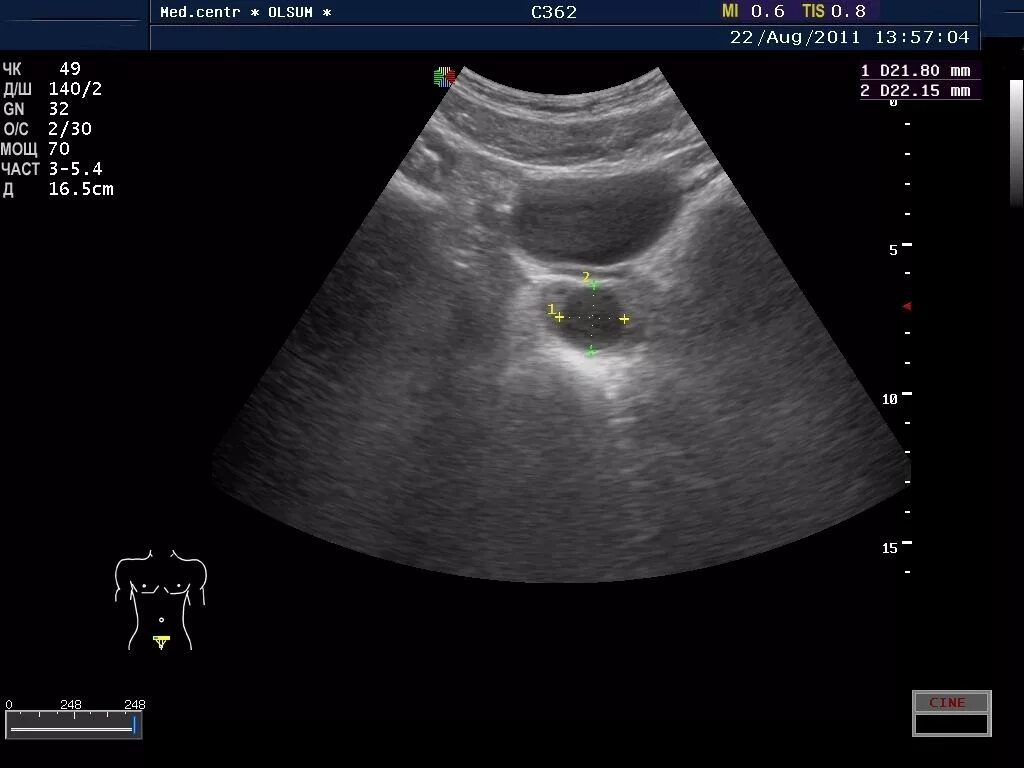

Фиброзные изменения предстательной железы